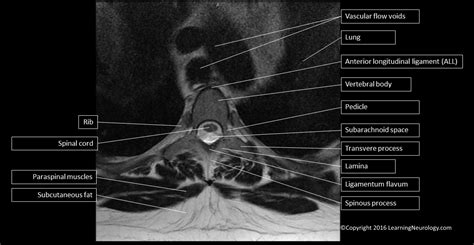

Axial view of the spinal MRI demonstrating thecal sac i ...

Axial view of the spinal MRI demonstrating thecal sac i ... from openi.nlm.nih.gov. Per maggiori informazioni, visita il loro sito web qui.